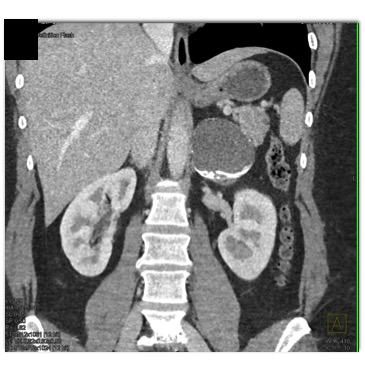

The most likely diagnosis in this case is

adrenal myelolipoma

old adrenal hematoma

pancreatic pseudocyst

adrenal carcinoma